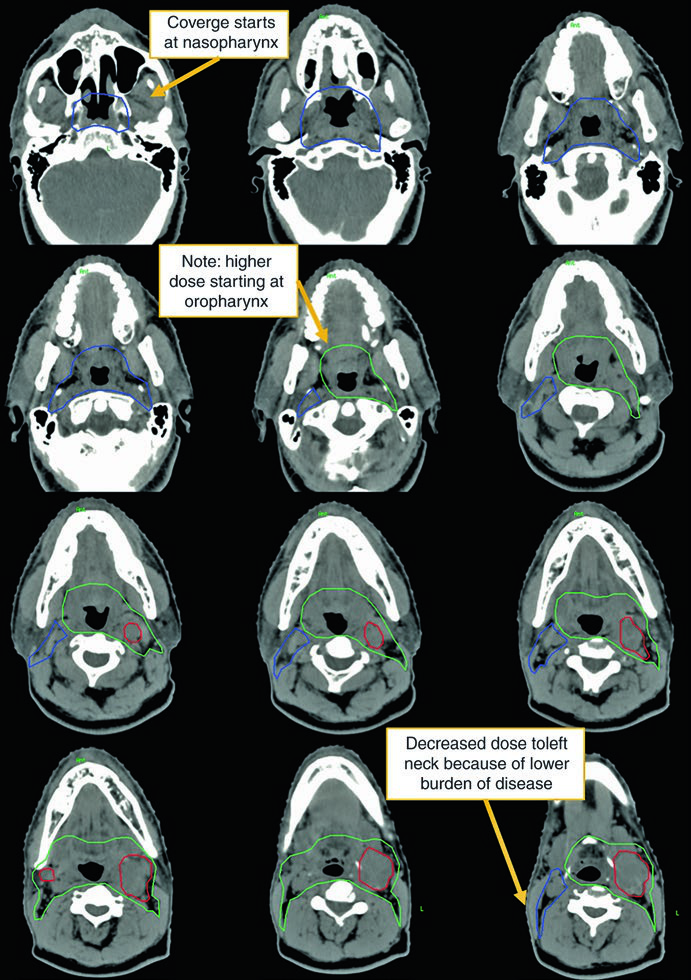

Observe a diferença entre o delineamento no pescoço operado (ipsilateral) e o contralateral. O CTV66Gy (vermelho) cobre o leito cirúrgico de alto risco; o CTV54-60Gy (verde) cobre as mucosas faríngeas em risco de abrigar o primário; e o CTV54Gy (azul) cobre o pescoço contralateral profilaticamente. Essa assimetria reflete o princípio de escalonar a dose conforme o risco real.

A visualização em cortes sagitais (Fig. 10.2) é particularmente útil para confirmar a extensão craniocaudal correta dos volumes de mucosa — nasofaringe, orofaringe e laringe/hipofaringe — e assegurar que não haja lacunas entre os CTVs adjacentes. O isocentro radiográfico serve como referência geométrica para o planejamento.

Neste caso, o CTV70Gy (vermelho) engloba a doença macroscópica bilateral; o CTV60Gy (verde) cobre as mucosas faríngeas em risco; e o CTV54Gy (azul) inclui todo o pescoço bilateral profilaticamente. A negatividade para HPV justifica a cobertura abrangente de toda a faringe, pois sem a orientação viral para um subsítio específico, o risco é distribuído ao longo de todo o eixo mucoso.